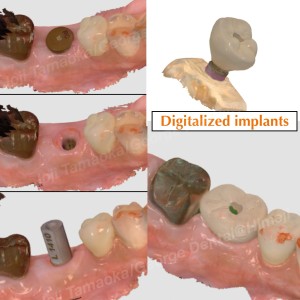

▶︎ デジタル技術による安全なインプラント手術

当院では、インプラント治療はすべて

🖥 デジタルシミュレーション + サージカルガイド

を使用しています。

• CTデータと口腔内スキャンを合成

• インプラントの最適ポジションを事前にミリ単位で設計

• 設計通りに正確に埋入できるガイドを作製

これにより手術の安全性が高まり、

神経損傷などのリスクを最小限に抑えた“予測性の高い治療”が可能となります。

今回もガイドを用いることで、短時間で正確な埋入が実現しました。

▶︎ 補綴(かぶせ物)もフルデジタルで精密に

インプラントの上に装着するかぶせ物(セラミッククラウン)も

すべてデジタルで作製。

• 型取りは光学スキャナーで快適

• 高精度な設計により噛み合わせも自然

• 歯ぐきとのフィットも良好

仕上がりも非常に自然で、噛む機能も問題なく回復しています。